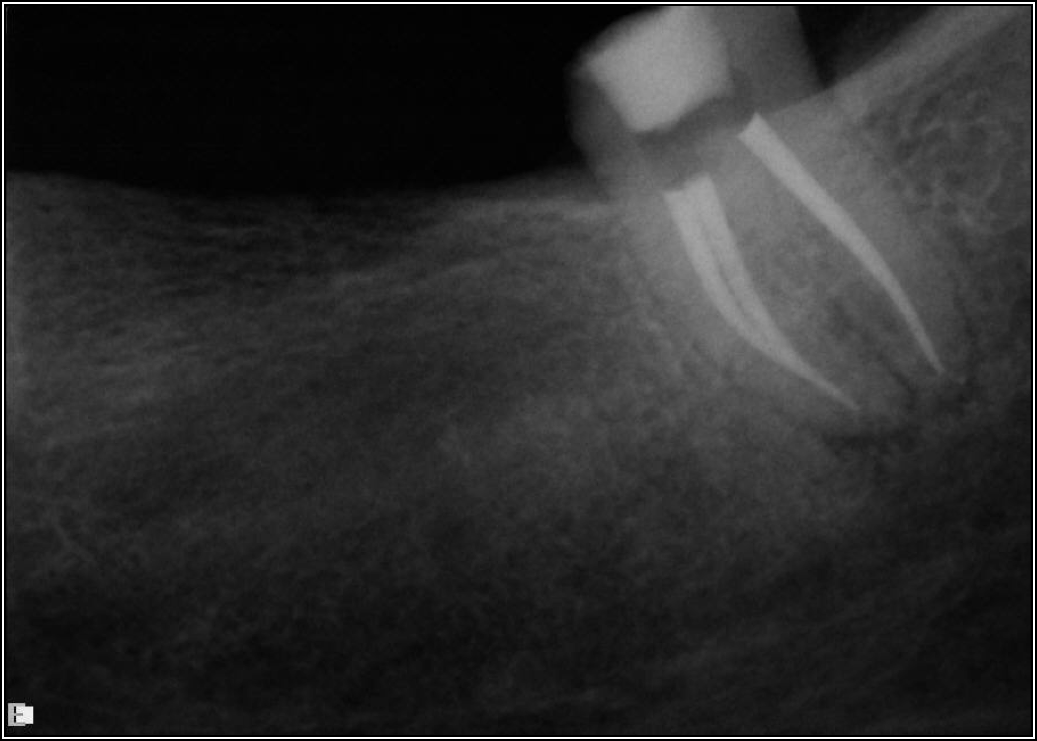

If a tooth stands alone, greater forces will be placed on it because it has no adjacent teeth to provide support. This situation will affect the decision-making process for placing a post. Figure 3 shows a tooth that was on an island and would be having three implants placed in front of it. The tooth would take a much greater beating than another tooth that had support proximally. Even though it had a good root canal, the clinician would need to account for whether the tooth would last until the implants integrated. Figure 4 shows a case that would quickly proceed to implants. The patient had a less-than-ideal bridge for over a decade, with decent endodontics and functionality. There was also an overhang on the premolar. The post was not ideal in this case because there was one distal canal and not all the gutta-percha was removed from it. An intimate fit should be the goal with the post and the walls. Whether using a threaded or non-threaded post, there should not be excess gutta-percha because it is not as solid as the tooth and will lead to greater movement. That movement on the tooth and bridge will create too much force and result in demise.

Fig 3. Tooth on an island.

Figure 3